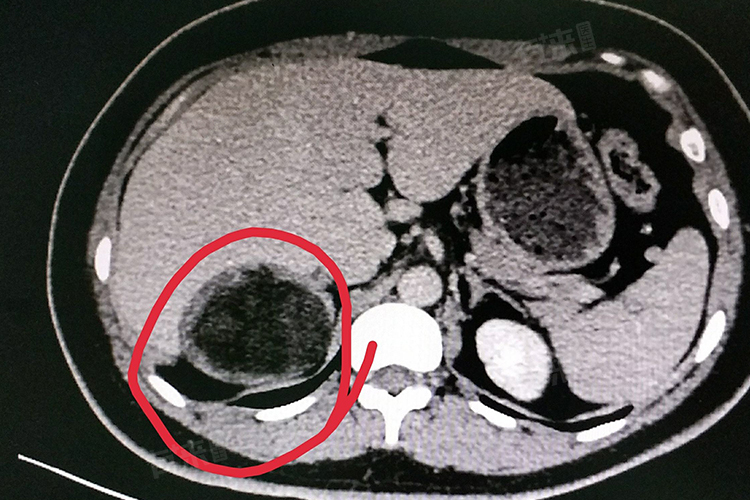

- 髓样脂肪瘤的诊断主要依靠影像学检查,其中B超是最常用的筛查方法。CT和MRI等影像学检查也可以提供更为详细的信息,有助于明确肿瘤的大小、位置和与周围组织的关系。